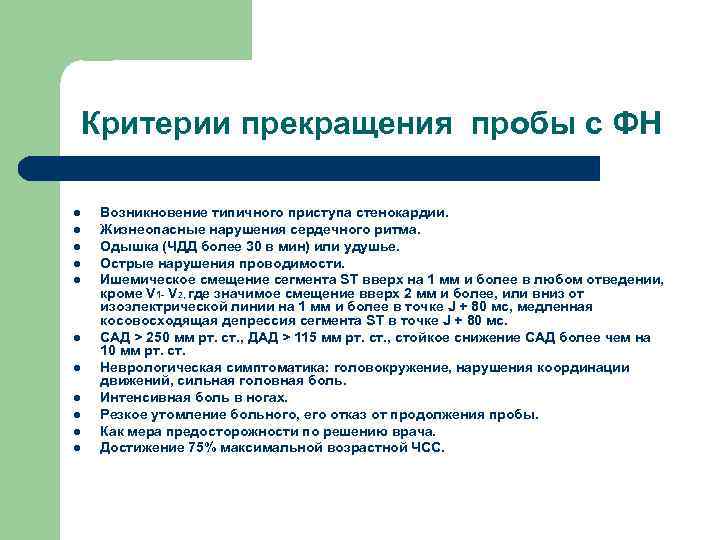

Критерии прекращения пробы с ФН l l l Возникновение типичного приступа стенокардии. Жизнеопасные нарушения сердечного ритма. Одышка (ЧДД более 30 в мин) или удушье. Острые нарушения проводимости. Ишемическое смещение сегмента ST вверх на 1 мм и более в любом отведении, кроме V 1 - V 2, где значимое смещение вверх 2 мм и более, или вниз от изоэлектрической линии на 1 мм и более в точке J + 80 мс, медленная косовосходящая депрессия сегмента ST в точке J + 80 мс. САД > 250 мм рт. ст. , ДАД > 115 мм рт. ст. , стойкое снижение САД более чем на 10 мм рт. ст. Неврологическая симптоматика: головокружение, нарушения координации движений, сильная головная боль. Интенсивная боль в ногах. Резкое утомление больного, его отказ от продолжения пробы. Как мера предосторожности по решению врача. Достижение 75% максимальной возрастной ЧСС.